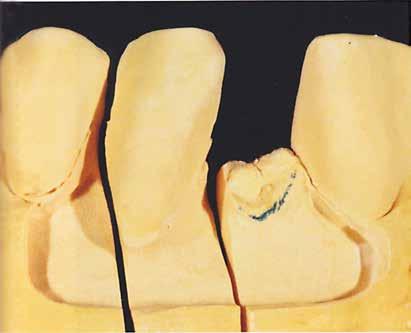

A laboratóriumban szekciós minta készült, blokk-stiftekkel (1. kép) , amelynek készítése során nagy figyelmet szenteltünk az ínymaszk (Majesthetik- Gingiimplant picodent) és a felfekvő lengőtag területének (2–6. képek)

A minta beolvasása után számítógéppel terveztük meg a híd vázát (7. kép). 0,06 mm-es cementrést terveztünk a teljes karfelület alá, 1 mmre végződve a preparáció szélétől (8–11. képek)

Így egyenlítettük ki a kötésjavító vastagságát, sikeresen. Az adatokat elküldtük az AHRtec-frézközpontba, néhány nap múlva visszakaptuk a cirkonvázat (12. kép). A marási paraméterek optimális betartása következtében a passzítás egyszerű volt (13. kép)

Most következett a legfontosabb lépés: a szárny belső felületét HotBond-dal fújtuk le (14. kép). Ez üvegszerű, savazható kerámia, amely beszívódik a cirkonba, és optimális kötést eredményez a pillérfogon.

A leszórt felszínnek porszerűnek kell lennie. A széli fölöslegeket az infiltrációs égetés előtt el kell távolítani, különben pontatlan lesz az illeszkedés (16. kép)